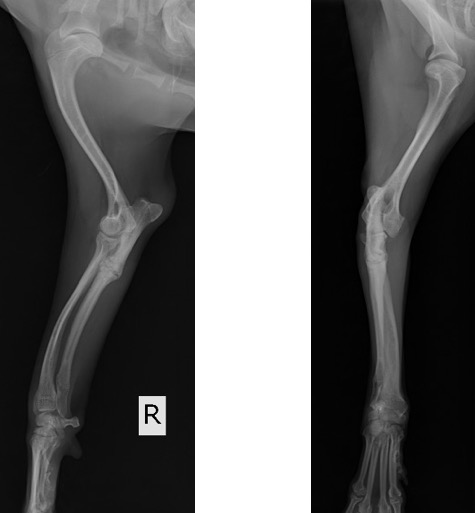

単純X線画像検査において、右側の尺骨遠位成長板領域の不透過性亢進、橈骨の頭側湾曲、鈎状突起と上腕骨顆の間隙が広がっている所見が認められたため、尺骨遠位成長板早期閉鎖が疑われました。

前腕の側面像 (黄丸;尺骨遠位成長板の不透過性亢進 青矢印:橈骨の湾曲 赤矢印:鈎状突起と上腕骨顆の間隙)

前腕の頭尾側像 (黄丸:尺骨遠位成長板の不透過性亢進 青矢印:橈骨の湾曲)